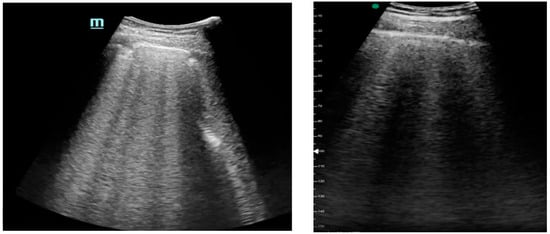

Figure 1, Figure 2 and Figure 3 exhibit characteristic examples of ultrasound still images from the videos captured via a standard ultrasound (left side) and portable handheld device (right side). Quality may slightly differ from that of the videos as these are still images.

Figure 3. Simple pleural effusion with atelectasis.